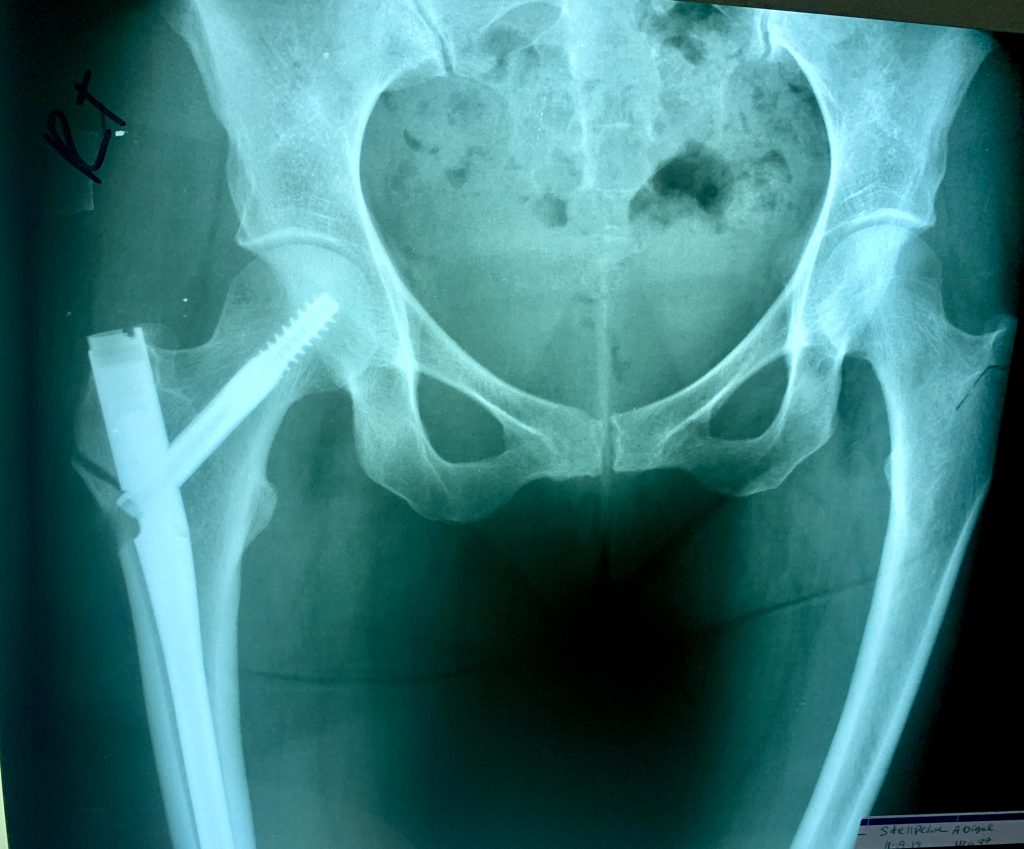

I started working with Dr. Goolsby and Dr. Serota in 2018 when I got a stress fracture in my left hip while training for the 2018 NYC Marathon. I was then diagnosed with osteoporosis and the injury took an abnormally long time to heal because of this. They got me running again and in 2019 I was PRing in every race that I did and had amazing training going into the 2019 NYC Marathon where I hopped to BQ. My dreams were cut way short when my right hip and femur spontaneously broke at Mile 14 of the race and I was taken off the course in an ambulance. I spent 5 days in a Queens hospital and have a metal rod in that right leg/hip. One of the first things I did in that ER on Sunday Nov 4, 2019 was reach out to Dr. Goolsby, who picked up on a Sunday, to seek her advice and start the wheels turning to come under her care because I trusted her completely. After months of rehab and working with Dr. Serota and Dr. Goolsby to improve my bone health, treat my RED syndrome, and heal my hip I was able to slowly resume running in the summer of 2020. After another setback in the spring of 2021, we determined my bones weren't yet ready to marathon. But after 3 long years and 3 days since I first was taken off the marathon course, I was able to complete the 2022 Marathon on Nov 6.